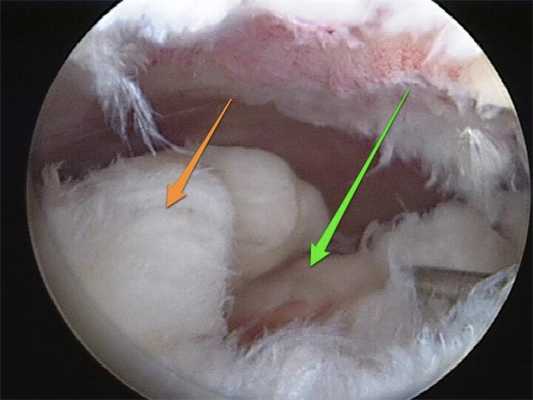

![]()

Изображение полости сустава.